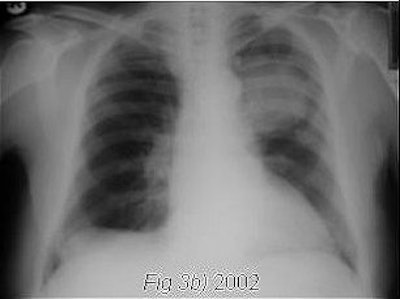

| Images A and B are both examples of left ventricular function masking neoplastic lesion in left upper zone. Images courtesy of Dr. Devaki Gnananandha. |

Overall, in seven of 44 chest films reviewed in this series, diagnosis was delayed due to failure of the follow-up system for abnormal reports. Four of the seven cases involved a failure to repeat films. In most of the abnormal chest films, the lesions were hidden within the hilum or behind the heart, or were obscured by edema related to left ventricular dysfunction.